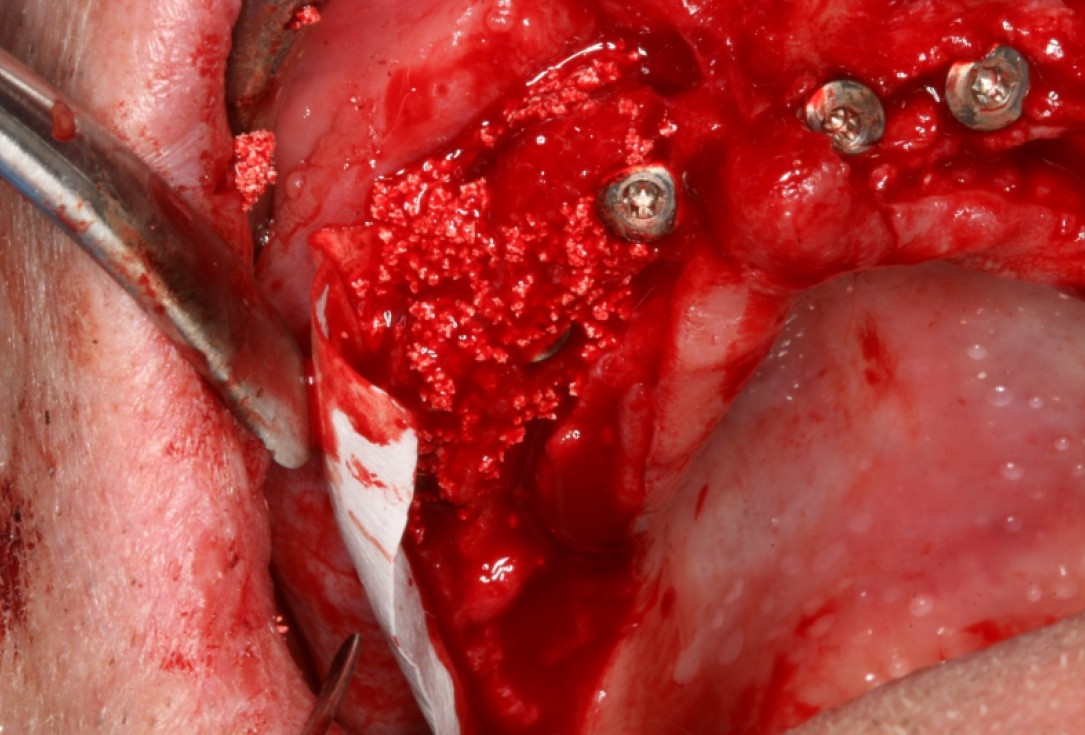

04/10 - Lateral deposition of maxresorb® to prevent resorption of the vestibular wallCircular bone splitting with maxresorb® & collprotect® membrane - PD Dr. J. Neugebauer